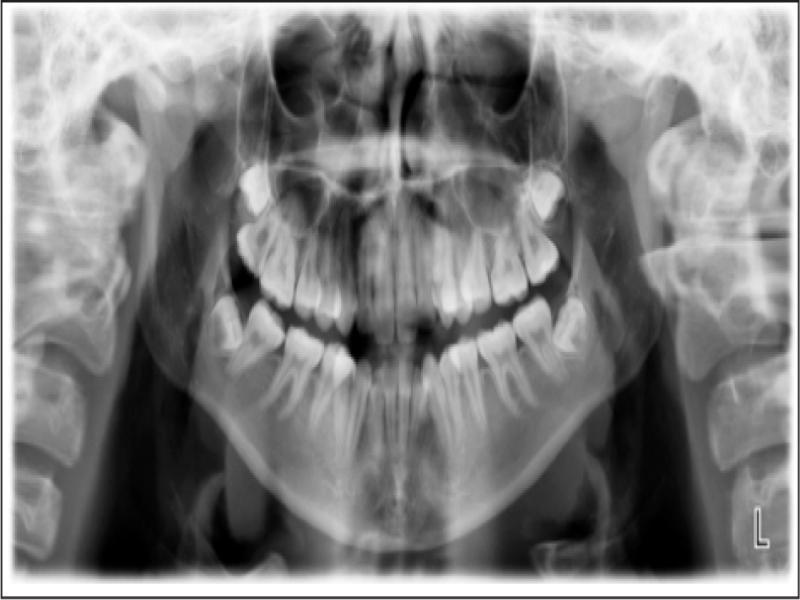

A radiographic examination was unremarkable on the OPG (Figure 2). Cephalometrically (Figure 3, Table I) a Class III skeletal relationship was evident, with a Wits discrepancy of -2.1 mm (due primarily to maxillary retrusion – SNA 72.6°). However, the Class III was camouflaged by the significant vertical disproportion, highlighted by an increased mandibular plane angle (28.6°), reduced facial axis angle (83.2°), reduced Jarabak’s ratio (56.5%), and increased lower anterior facial height (53.4%), all of which indicated a dolichofacial pattern. The maxillary retrusion, combined with a mandibular downward and backward rotation, resulted in a bimaxillary retrusive skeletal relationship (SNB 72.6°). The upper incisors were at an acceptable angulation relative to the palatal plane (112°) and the anteroposterior position relative to Na-Vert. The lower incisors were at an acceptable position relative to APo but were retroclined relative to the mandibular plane (80.7°) according to mesofacial norms.

Pretreatment OPG.